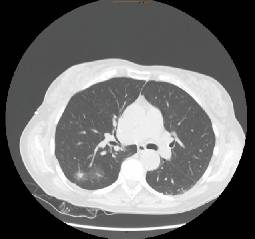

Zusätzlich besteht das Risiko eines Zweitkarzinoms der Lunge, welches in der Literatur mit 3–6 % pro Jahr angegeben wird [3]. Während lokoregionäre und Fernmetastasen zumeist systemisch therapiert werden, können Lokalrezidive und vor allem Zweitkarzinome eventuell einem kurativen Therapieansatz zugeführt werden (Abb. 1). Dabei gilt gleich wie für jedes Lungenkarzinom: Ein kurativer Ansatz ist nur im Frühstadium möglich. Es bedarf daher einer optimalen onkologischen Nachsorge um ein solches Zweitkarzinom frühzeitig zur detektieren.

Abb. 1

Zwei Areale eines multifokalen BAC-Rezidivs mit histologisch gesicherten invasiven Anteilen eines Adenokarzinoms